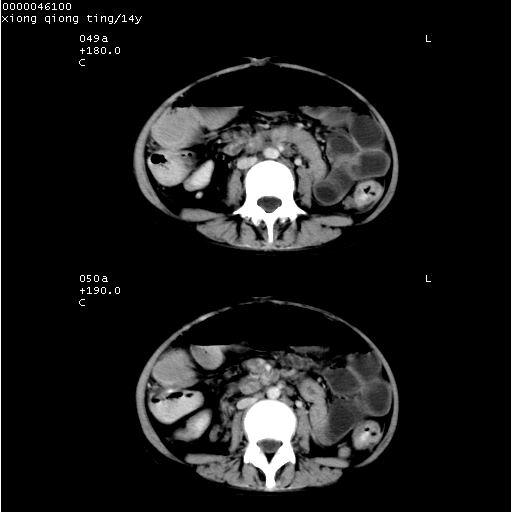

中下腹及盆腔ct轴位平扫+增强扫描(层厚10mm,螺距1.0,重建间隔10mm),图像如下:

(注:患儿检查当日上午9时口服胃肠道对比剂,下午3时许行ct扫描检查,未行对比剂直肠保留灌肠,检查当日患儿腹泻)

中下腹及盆腔ct轴位扫描(ps+ce)提示:腹部肠管明显充气扩张,并见数个不同宽度之气液平面;疑不全性肠梗阻或肠郁张。临床会诊考虑为患儿腹泻,肠郁张所致;后来未经特殊处理,患儿大便恢复正常,亦无腹胀。